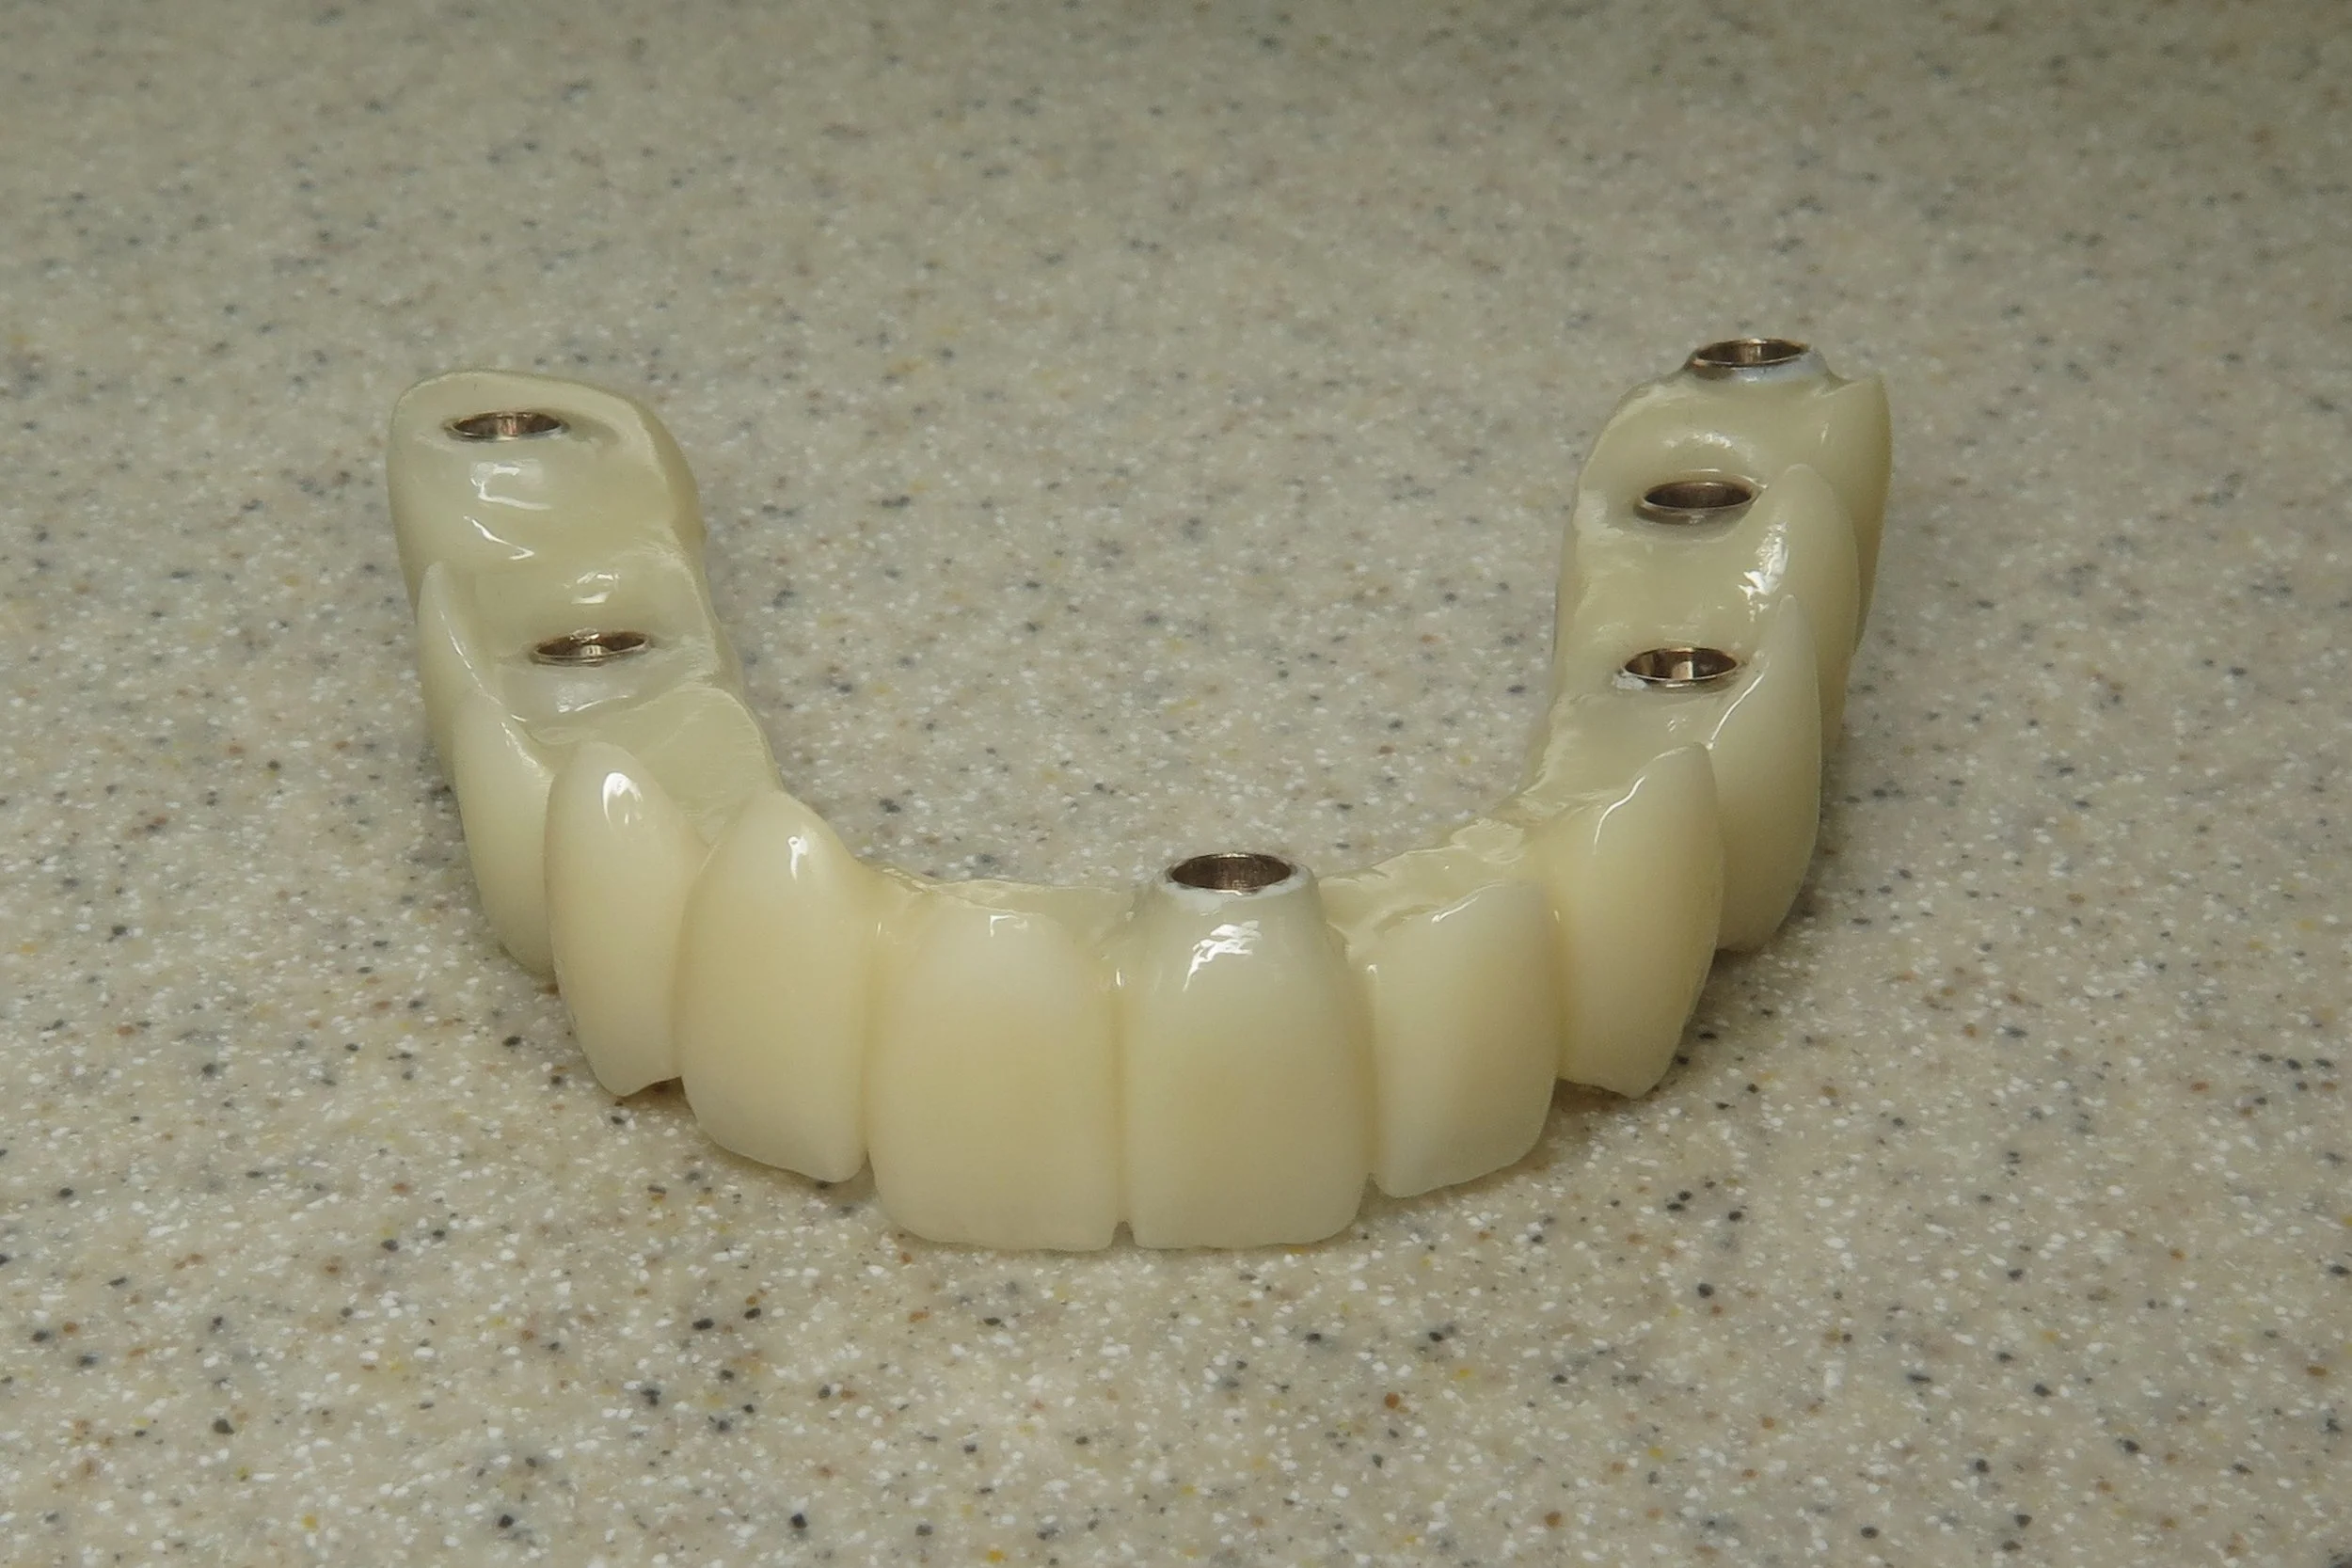

The Conus Implant Bridge is a restorative solution created by Dr. Johansen for patients that are missing all or some of their teeth in either the upper or lower arches. The Conus Implant Bridge is a unique, friction-retained prosthetic that eliminates the problems associated with both cement and screw retained implant bridge work. It retains all of the benefits of a fixed prosthetic with the cleansable aspect of a removable prosthetic. It’s the best of both worlds. It’s more cost effective and conservative than an All on 4 and it’s more versatile and cleansable than a 3 on 6 option.

4. Bridge

The following cases were done by Dr. Johansen: